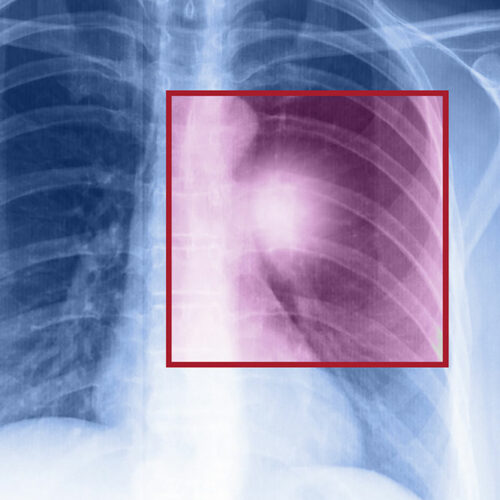

Lung cancer – Types, symptoms, and causes

When the cells in the lungs begin to abnormally multiply and grow, it results in cancer. Lung cancer is one of the leading causes of death in the world. And the risk of suffering from this life-threatening disease is even higher when one is a smoker. Herein, we discuss the various factors that come into play when it comes to lung cancer. Symptoms of lung cancer Usually, lung cancer does not present any symptoms or signs in the early stages. However, as the disease progresses, one may notice Headache Bone pain Loss in weight Hoarse voice Chest pain Shortness of breath Coughing of blood A new cough that persists One should consult a doctor if they notice these signs.